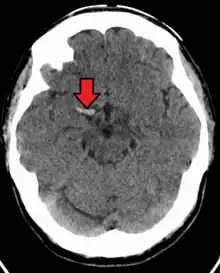

Cerebral venous sinus thrombosis

Cerebral venous sinus thrombosis (CVST) is a rare form of stroke which results from the blockage of the dural venous sinuses by a thrombus. Symptoms may include headache, abnormal vision, any of the symptoms of stroke such as weakness of the face and limbs on one side of the body and seizures. The diagnosis is usually made with a CT or MRI scan. The majority of persons affected make a full recovery. The mortality rate is 4.3%.[8]